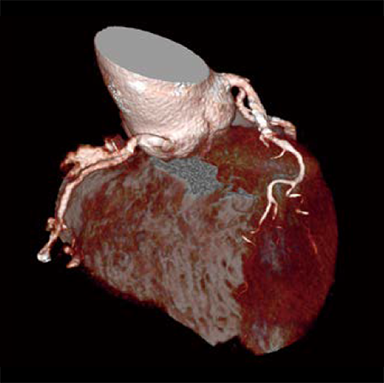

Dans les examens TDM cardiaques, les différents facteurs tels que la fréquence cardiaque et les mouvements du cœur affectent la qualité de l’image. Avec les méthodes conventionnelles de reconstruction d’image, des artères coronaires non focalisées et des artefacts causés par le mouvement peuvent apparaître, ce qui se traduit par des images ne répondant pas à la qualité attendue, ce qui peut affecter le diagnostic. Pour résoudre ces problèmes, Fujifilm a développé Cardio StillShot, qui calcule la direction et la quantité de mouvement du sujet en quatre dimensions à partir des données brutes collectées pendant les examens TDM cardiaques, et les corrige pendant la reconstruction de l’image pour obtenir une résolution temporelle effective de 28 msec.*1 La résolution temporelle effective contribue à améliorer la capacité de diagnostic en fournissant des images cliniques focalisées de haute définition avec moins d’artefacts de mouvement, même chez les patients ayant une fréquence cardiaque élevée.

Cardio StillShot : OFF

ON